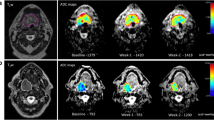

The workflow in our prospective study including the inclusion of eligible patients, delineation of the primary tumor and lymph node metastases of the final included patients, the extraction of quantitative imaging parameters, and metastases predictive assessment of locoregional recurrence-free survival and overall survival using the extracted parameters of the primary tumor and lymph node

Associations of imaging parameters per subgroup

Seventy PT ROIs were drawn and 59 lymph node metastasis ROIs (largest LNM) on each modality (Table 1). The comparison of both observers resulted in no significant different values and a high interobserver correlation (Supplement 1). A Dice index in primary tumors of 0.88 at the DWI/IVIM and 0.85 at DCE delineation was found (not tabulated). For LNM, a Dice index of 0.97 at DCE and 0.92 at DWI/IVIM delineation was found (not tabulated). Primary tumor ADCGTV, D, f, and D*, DCEGTV, and all 18F-FDG-PET values (Supplement 2) were significantly higher in advanced T-staged tumors (all p ≤ 0.02). In advanced N-staged tumors, PT ADCGTV and Ve were significantly higher (p = 0.021 and p = 0.023, respectively). In HPV-negative tumors, ADCmean, D, D*, SUVmax, SUVmean, and SUVpeak were significantly higher than HPV-positives (p < 0.043). In patients with intoxications, ADCmean, D, and D* were significantly different among the different categories (all p < 0.027).

In LNM (Supplement 3), Kep and all 18F-FDG-PET parameters were significantly higher in advanced N-stages (p = 0.025, p ≤ 0.016, respectively). In HPV-negative tumors, D was found to be significantly higher (p = 0.002) and D* lower (p = 0.007) than in HPV-positive tumors. In patients with intoxications, f was found to be significantly lower (p = 0.026).

Inter-modality correlations

The inter-modality correlation in PT between 18F-FDG-PET-, DWI/IVIM-, and DCE-derived parameters (Supplement 4) was only significant among GTV parameters (ADCGTV, DCEGTV, TLG, and MATV), SUVpeak, and SUVmean (range: r = 0.434–0.915). In LNM (Supplement 5), only volume parameters of LNM ADCGTV, MATV, and DCEGTV correlated significantly (range: r = 0.399–725). The intra-modality correlation for PT and LNM (Supplement 6) resulted in significant internal moderate correlation of ADC parameters (range: r = 0.432–0.794) and DCE parameters (r = 0.637–0.741) and high correlation of 18F-FDG-PET parameters (r = 0.409–0.995).